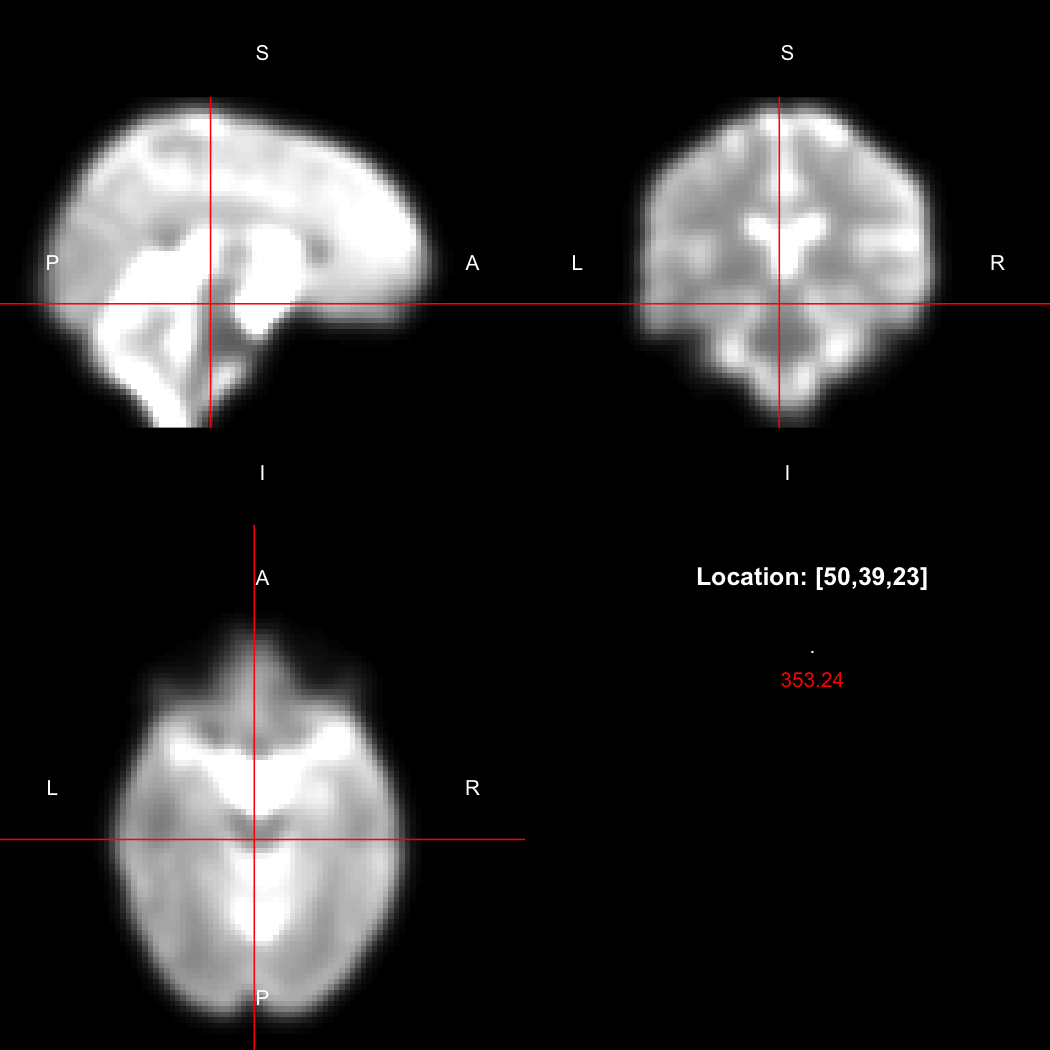

However, the pipe syntax provides an alternative, which can be

further simplified because calling view() on a pipeline

will implicitly run it.

image %>% smooth_gauss(4) %>% view()

## Setting window to (0, 549.9)

Notice now smooth_gauss() is now called with only one

argument, and view() with none, because the input to the

pipe (%>%) is implicitly added first. The benefits to

readability of this approach increase substantially as more operations

are added to the chain: